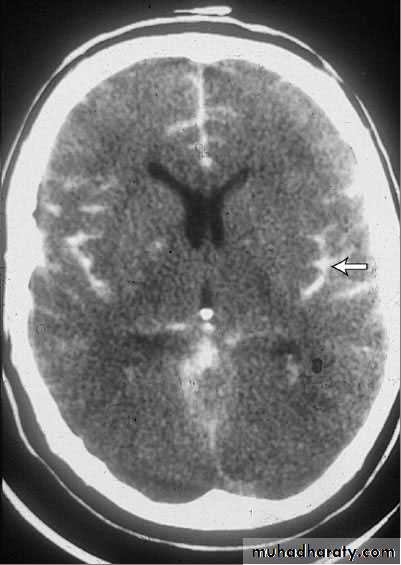

Subarachnoid Hemorrhage

Noncontrast CT is > 90% sensitive and is particularly sensitive if it is done within 6 h of symptom onset. MRI is comparably sensitive but less likely to be immediately available. False-negative results occur if volume of blood is small or if the patient is so anemic that blood is isodense with brain tissue. If subarachnoid hemorrhage is suspected clinically but not identified by neuroimaging or if neuroimaging is not immediately available, lumbar puncture is done .